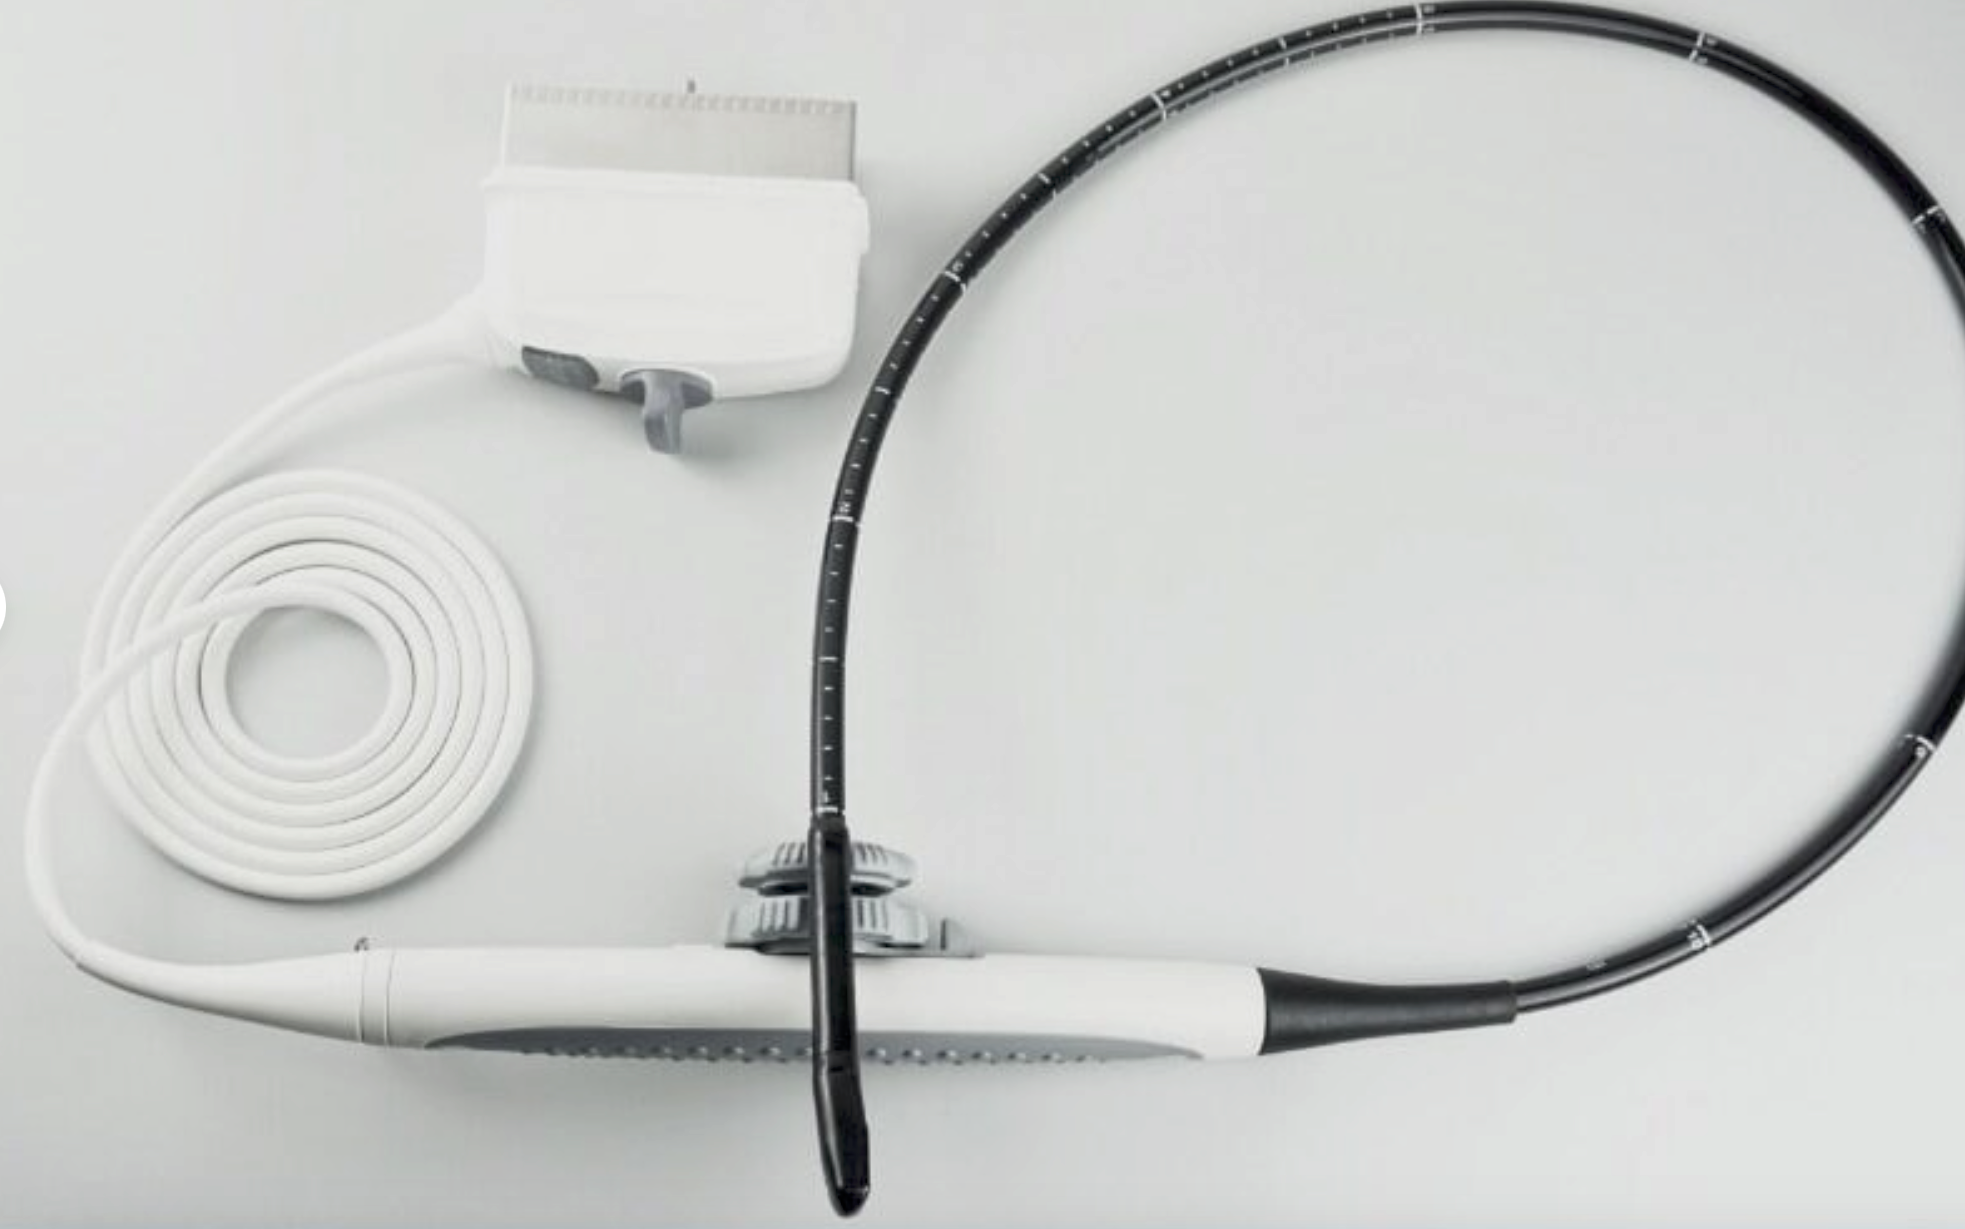

The Laptop Ultrasound scanner integrates cutting-edge technology and high-resolution imaging, making it an essential tool for medical professionals. It features a Transvaginal probe, which allows for detailed examinations of female reproductive organs, ensuring that healthcare providers receive the most accurate information possible. This technology minimizes discomfort and enhances patient care because it offers excellent visualization without needing invasive procedures.